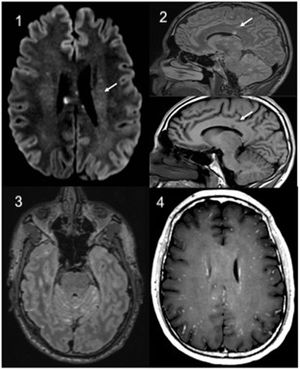

Complementary studies: haemogram, general biochemistry, C reactive protein and coagulation, normal. Lumbar puncture showed hyperproteinorrhoea, with Gram, panbacterial and myobacterial negative PCR. Lues serologies, HIV and neurotropic virus, as well as ANA, ANCA and HLA-B5 were negative. A video-EEG showed signs of mild diffuse encephalopathy and cranial CT was normal. Cranial MRI showed multiple supra-and intratentorial punctiform lesions in leptomeninges and “snowball” corpus callosum lesions (Fig. 1).

Brain MRI: 1: Axial. Diffusion with hyperintense punctiform lesions in relation to microinfarcts. 2: Sagittal, T2 Flair and T1 sagittal. Characteristic involvement of the corpus callosum. 3: Axial T2 Flair with contrast. hypersignal and leptomeningeal enhancement (additive signal T1 contrast + T2). 4: Axial T1 contrast with “military” uptake pattern.